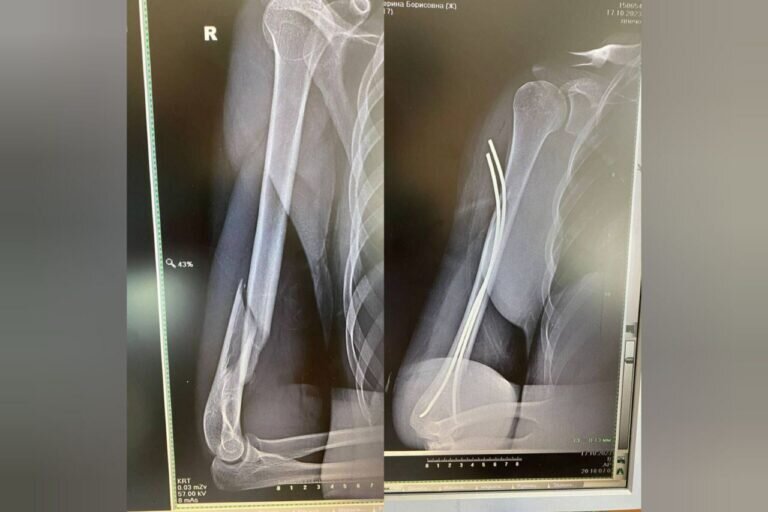

Девочка-подросток упала и сломала руку. Ее доставили в хирургическое отделение Областной детской клинической больницы с переломом плечевой кости со смещением.

Еще несколько лет назад девочке бы предстояла сложная операция открытого типа и долгие месяцы жизни с громоздкой металлической конструкцией в руке, сообщили в ОДКБ.

Однако сейчас хирурги имеют все возможности, чтобы провести малоинвазивную операцию.

В руке девочки через маленькие разрезы установили тонкие титановые конструкции, которые затем будут также удалены.